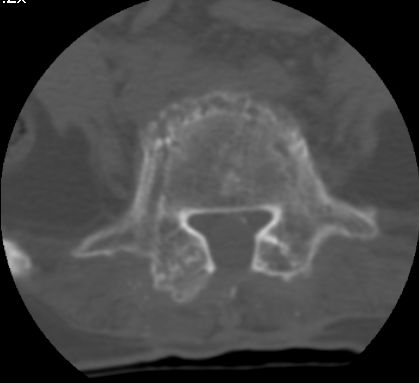

以下是引用余辉在2007-9-4 21:00:00的发言:[br]椎体棘突有点异常(像是被切割了),不知有否手术史,如椎体融合术等。单纯的退行性变可以出现椎间隙变窄,但同时一般会出现椎体上下缘的硬化增生,且椎体间完全融合的机率更小,本例椎体完全融合且椎体上下皮质缘破坏掉了,如果没有手术史,就应该考虑椎间盘炎性病变了,且椎体棘突及棘间韧带的变化也并不是不支持这个,多数小关节也融合了,且其形态也容易让人联想到如强脊炎及类风关等病变。[br][br][本贴已被 余辉 于 2007-9-4 21:03:55 修改过]

以下是引用chry3在2007-9-4 20:42:00的发言:[br]椎间盘病史?是什么样的病史,无双下肢放射痛,那就不是椎间盘突出了。是感染、什么性质的?[br]从图象看椎间隙消失,椎间盘组织未见,锥体滑脱是因为椎间盘溶解造成的[br]l4、5椎体骨质结构未见异常,l5上缘是l4的长期压迫所致[br]还是考虑椎间盘感染,结核。[br]